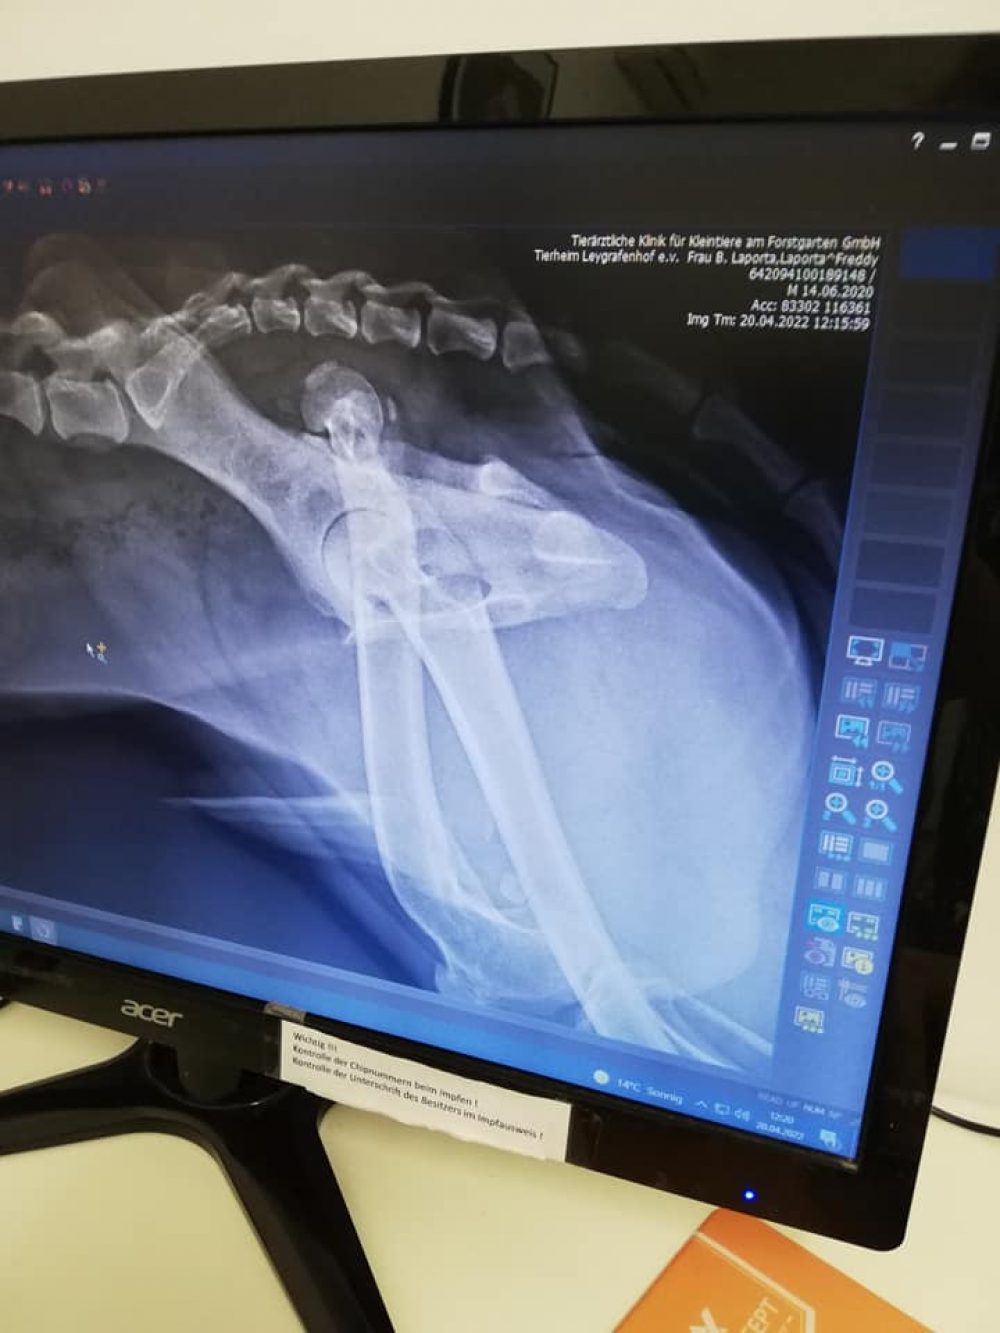

Er wurde bereits auf Herzwurm, Ehrlichiose, Borreliose und Leishmaniose getestet und alles war negativ. Doch leider wurde beim Tierarzt Check festgestellt, dass am linken Bein der Hüftknopf raus ist und dass das Knie falsch zusammen gewachsen ist. Diese Schäden scheinen schon länger vorzuliegen.

Freddy hat seine OP sehr gut überstanden und sucht nun seine Familie für immer ! Sein Hinterbein wird zwar immer etwas kürzer bleiben aber er kann damit gut und ohne schmerzen leben ! Da er sehr gerne bei seinen Menschen ist würde sich der freundliche zugängliche Rüde sicher gut als Bürohund machen. Wir wünschen ihm das sich bald jemand meldet damit auch er endlich richtig ankommen kann !